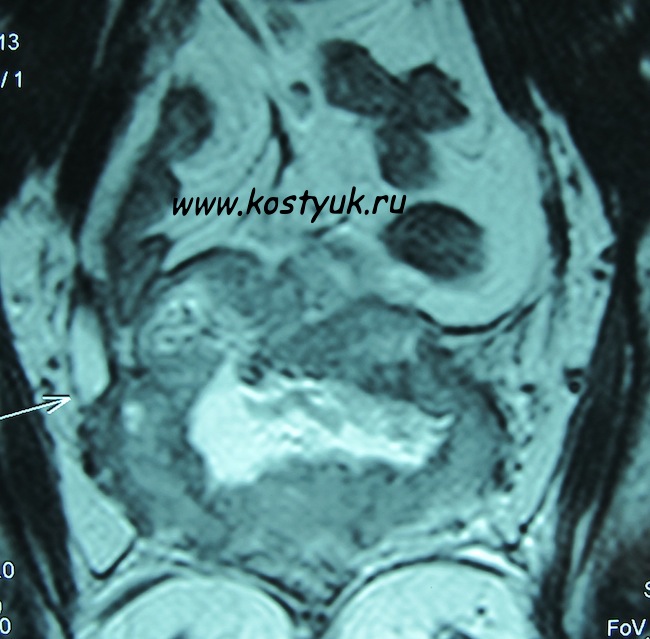

- МРТ малого таза.: из полости влагалища прослеживается свищевой ход в просвет прямой кишки в виде линейного неравномерного по толщине гиперинтенсивного МР-сигнала по Т2 ВИ, прямая кишка в ректосигмоидном отделе расширена, стенки неравномерно утолщены, слизистая сглажена. В проекции ложа матки определяется участок неоднородного изоинтенсивного МР-сигнала по Т2 ВИ, изоинтенсивного МР-сигнала по Т1 ВИ, солидной структуры, распространяющейся на прилежащие отделы прямой кишки, на область свода влагалища (преимущественно на переднюю и левую стенки), на заднюю стенку мочевого пузыря, размерами 5,4х3,2х2,7 см, после введения контрастного вещества определяется неравномерное усиление МР-сигнала от описанного участка структурных изменений. В мочевом пузыре отмечается утолщение задней стенки за счет вышеописанных изменений. Убедительных данных за увеличение лимфатических узлов не получено.